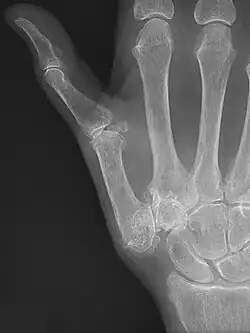

Stage 4 trapeziometacarpal osteoarthritis, with major subluxation of the joint

Stage 4:

• Narrow joint space

• Concomitant scaphotrapezial arthritis

X-ray of trapeziometacarpal joint replacement. Left hand of a 58-year-old woman.